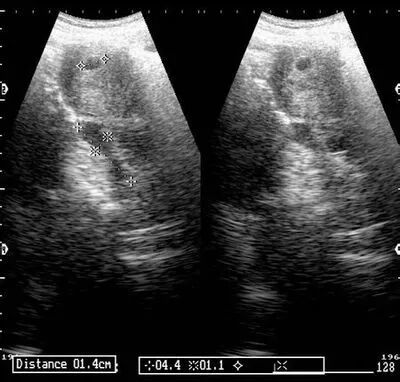

中午下班的丈夫见到依萍,吓坏了,立即将依萍送到医院,但是医院检查结果让依萍不敢相信……B超检查显示,依萍的宫腔内可见多个圆形、椭圆形不规则水泡状的东西,呈蜂窝状,就跟葡萄一样,根本没有胎儿、胎盘、羊水。

原来依萍怀的是葡萄胎,医生检查后发现,怀孕三个来月的肚子应该还不会隆起,可依萍的肚子却像怀孕五个月那么大,而据医生介绍,葡萄胎就是妊娠后胎盘绒毛滋养细胞增生,间质高度水肿,形成大小不一的水泡,水泡间相连成串,形状就像葡萄一样。葡萄胎的病人的子宫会明显大于停经的月份。